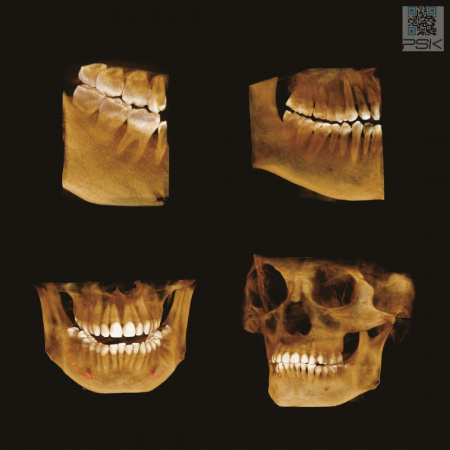

Умная Функция Уменьшения Артефактов от Металла (Smart Metal Artifact Reduction Function) – позволяет минимизировать артефакты от вторичного излучения металлов и получить необходимую диагностическую информацию для постановки корректного диагноза, а также планирования и контроля проведенного лечения.

Области сканирования (FOV), см 3.5×4, 4×5, 7×7, 8×8, 16×8, 16×14

Виды исследований Панорама, КТ